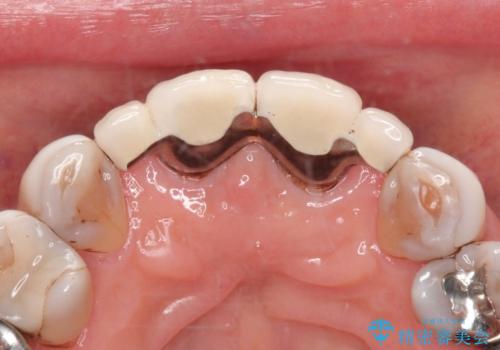

- 前歯の被せもののやりかえを主訴に来院されました。

前歯の歯茎から膿も出ていたため、歯内治療を行なったのち修復を行なっております。

根管治療および外科的歯内療法を行なってから被せものの処置を行なっております。